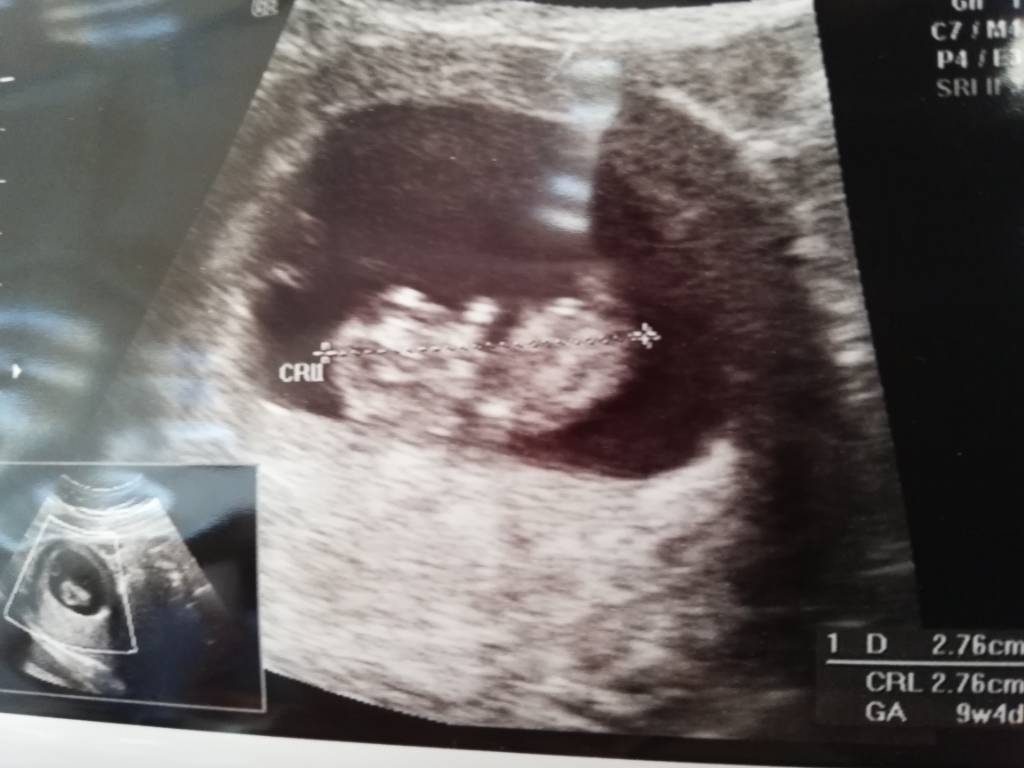

• IMG_20191030_081517.jpeg

IMG_20191030_081517.jpeg

58,1 KB · Wyświetleń: 173